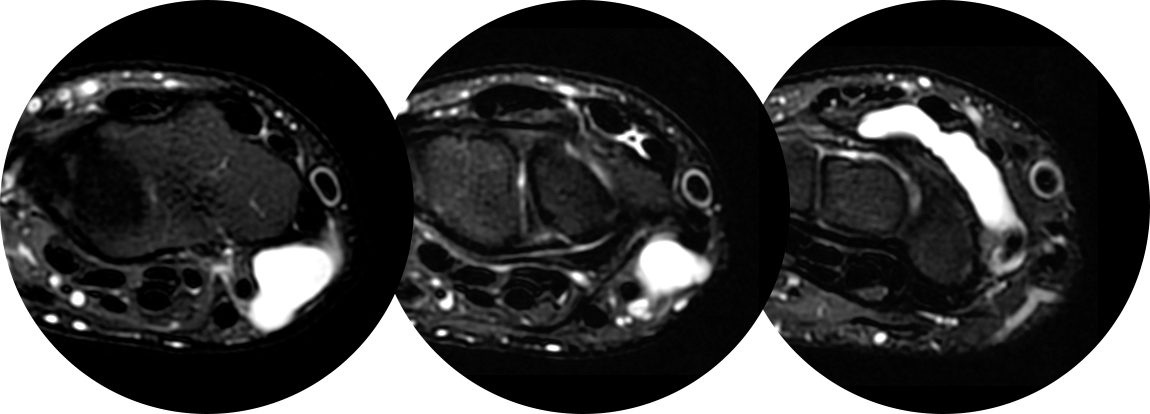

손등의 횡절개 방법은 가장 미용적이며, 상처에 의한 통증도 덜 남는 절개 방법으로 손등쪽 결절종에 경우 대부분 적용 가능합니다.

다음 사진들처럼 수술시 관절에 연결된 뿌리까지 찾아서 제거하여야 재발하지 않기 때문에 수술자의 기술이 특히 중요한 수술입니다.